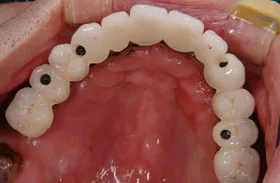

インプラントを使用した入れ歯の症例

■治療前

■治療後

| 主訴 | しっかりかみたい(咬合障害) |

| 治療方法 | 費用を抑える為、全てインプラントではなく、インプラントを土台とした入れ歯の治療 |

| 治療期間 | 約6か月 |

| 通院回数等 | 約20回 |

| 費用 | 約150万円 |

| リスク・副作用 | 術後の腫れ・痛み |